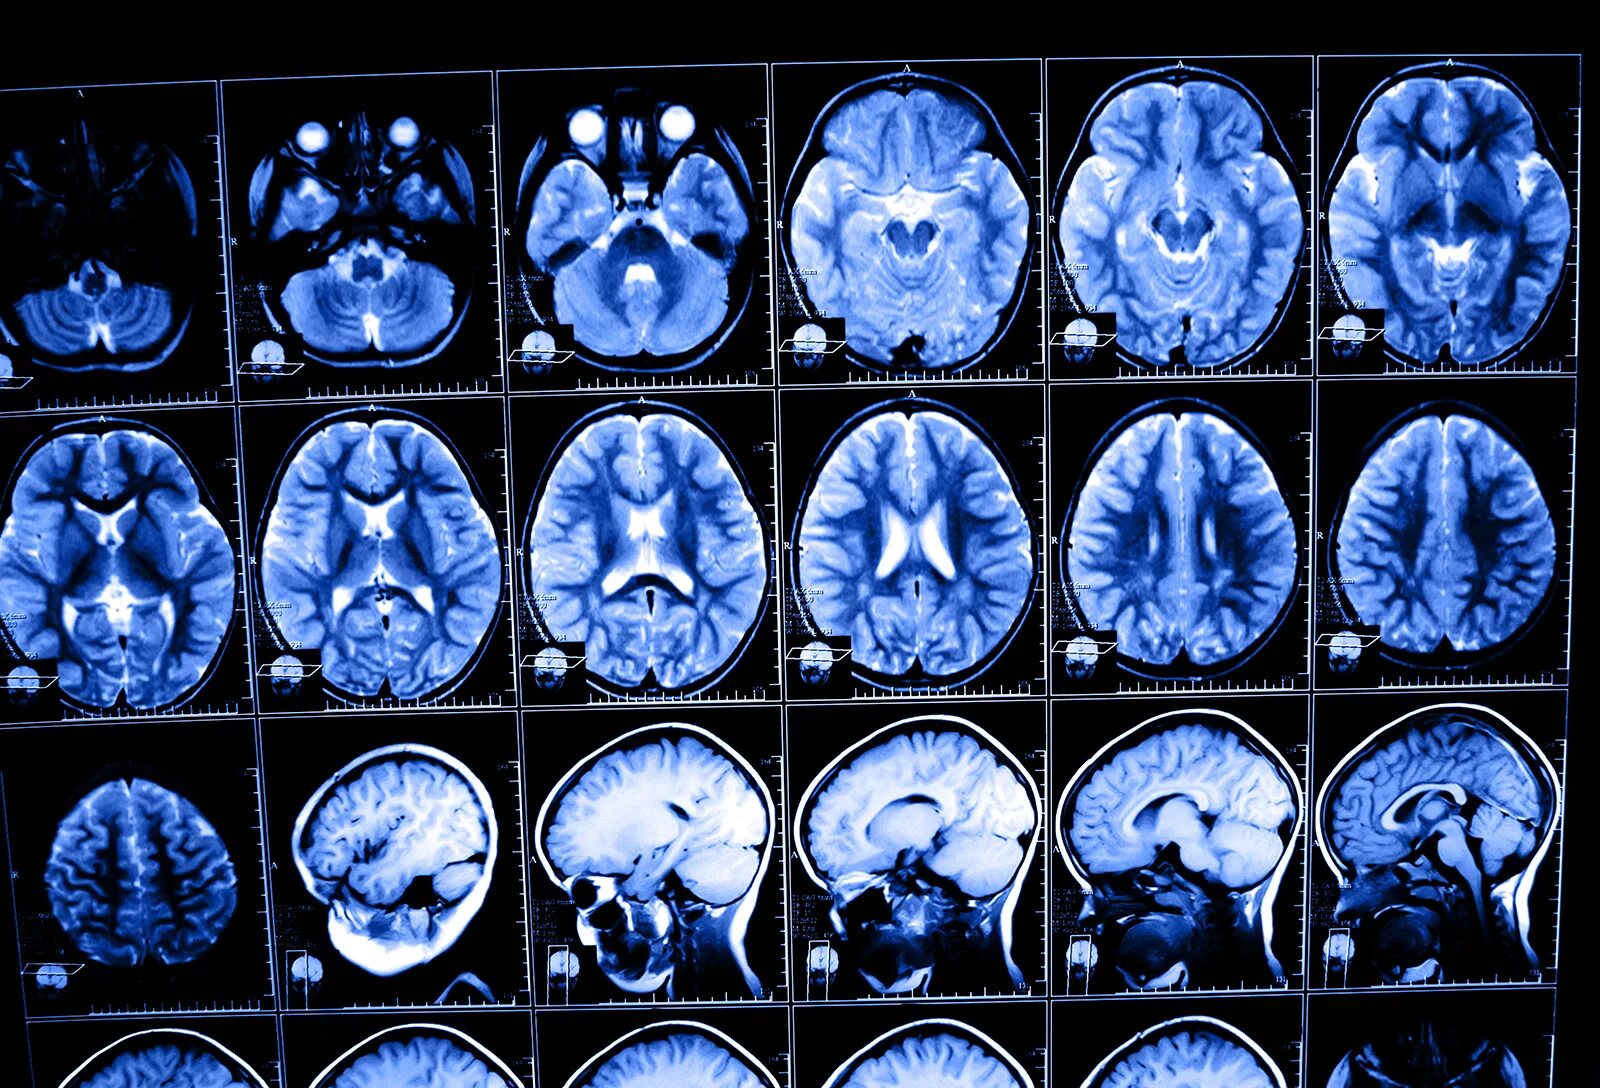

После мрт головного мозга